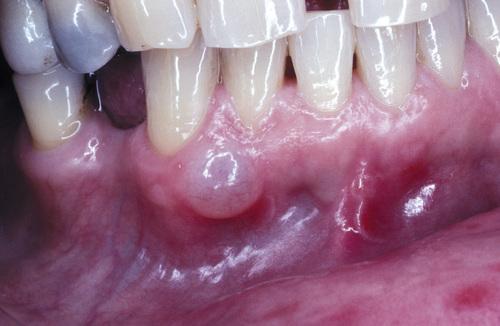

Tense, fluid-filled swelling on the facial gingiva. Surgical excision revealed superficial “cupping out” of the alveolar bone.

gingival cyst of the adult